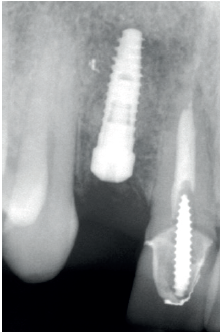

Cuatro meses después, se realiza un nuevo Cone-Beam dental para poder cuantificar la ganancia obtenida en anchura con el procedimiento regenerativo. Se observa en el corte seccional como se ha logrado una anchura de cresta de más de 7 mm y una regeneración completa del reborde alveolar, lo que permite la inserción de un nuevo implante dental en la posición adecuada (Figura 10). En la reentrada quirúrgica se constata la información del Cone-Beam con una integración total del material de injerto, tal como se muestra en las imágenes clínicas en el momento de la elevación del colgajo para la inserción del implante (Figuras 11 y 12). Se procede a la retirada del microtornillo y la colocación del implante, que se realiza mediante la compresión vestibular del injerto para ganar de esta manera aún más contorno en esta área (Figura 13). El implante se deja en una fase quirúrgica, con un pilar de cicatrización bajo que permita una localización posterior del mismo sin una cirugía agresiva del tejido blando para cuando se inicie la confección de la prótesis. El provisional sigue siendo una pieza en extensión desde el diente 1.1.